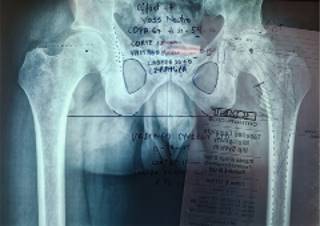

Tras los hallazgos radiográficos y la importante limitación de movilidad para el desarrollo de las actividades de la vida cotidiana, se propone y realiza recambio total de cadera izquierda mediante abordaje posterolateral. Durante el evento quirúrgico se observa de manera macroscópica la cabeza femoral, la cual muestra zonas de necrosis ósea y geodas en su interior (Figura 2). En cuanto a los componentes articulares, se utilizan componentes no cementados descritos a continuación: copa acetabular #54 (G7 Zimmer-Biomet), vástago corto #4 (Taperloc Microplasty Zimmer-Biomet), cabeza de cerámica #36 ± 0 mm y Liner 54/36 UHXLP (Figuras 3 y 4).

Figura 3: Planificación preoperatoria para el recambio total de cadera izquierda. Se decide el uso de componentes no cementados y un vástago corto (Taperloc Microplasty Zimmer) debido a la edad y actividad del paciente.